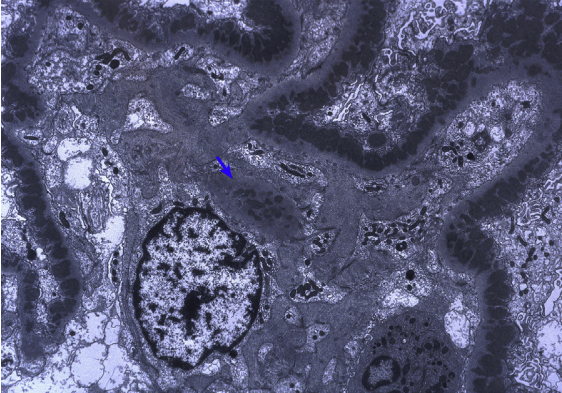

狼疮型肾炎Ⅴ型(膜性LN),大量上皮下电子致密物沉积,少量系膜区沉积(蓝色箭头)(电镜)

狼疮型肾炎Ⅴ型(膜性LN),大量上皮下电子致密物沉积,少量系膜区沉积(蓝色箭头)(电镜)